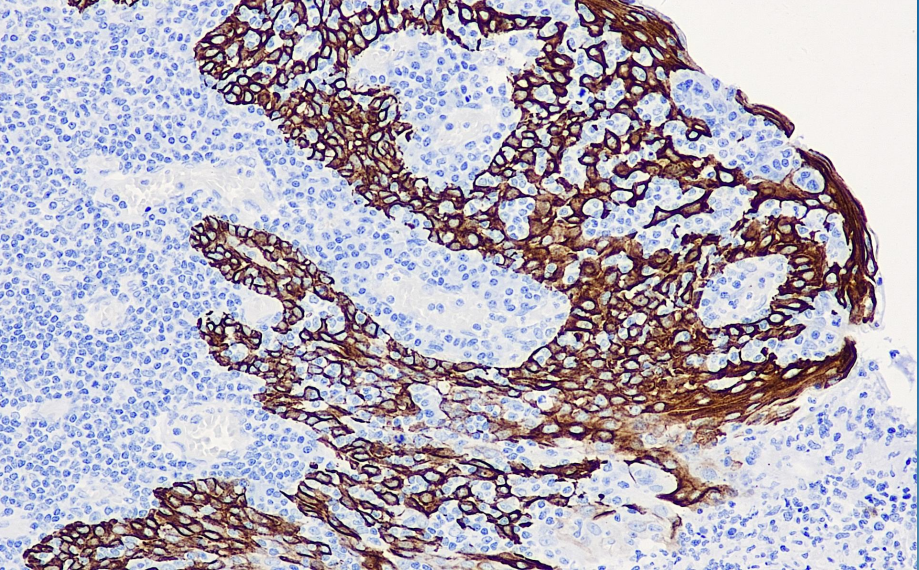

Positive control: tonsils

CK14 is a 50 kD cytokeratin expressed in complex epithelial cells and can also be used as a primary marker for squamous epithelium. It is generally used in combination with other CKs to identify whether tumor cells are derived from complex or monolayer epithelial cells.

CK14 antibody reagents can specifically bind to CK14 molecular antigens. Immunohistochemistry kits containing CK14 antibody reagents are suitable for the auxiliary diagnosis of squamous cell carcinoma and other single-layer epithelial carcinomas.